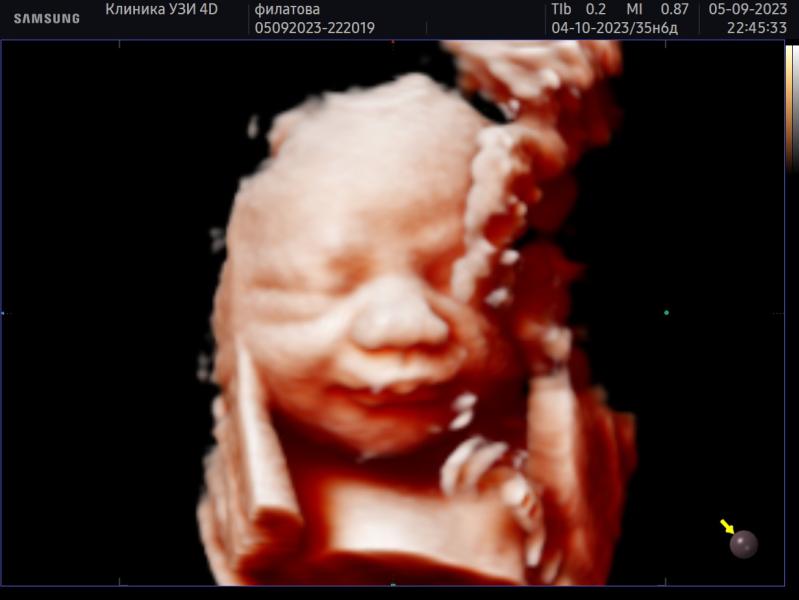

Фотосессия мини малыша: как прошла, параметры, сложности? Делимся опытом и переживаниями

Наша последняя фотосессия 🙏малыш миниатюрный будет как и дочь надеялась что будет чуть крупнее но нет, опять прогноз на 2800/2900🙏еле заставили руки и ноги с лица убрать😁